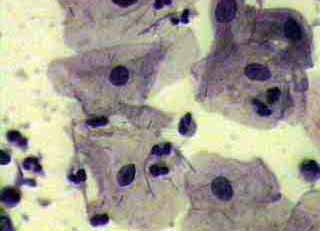

Ιατρικές Εικόνές - Πινακοθήκη κυτταρολογικών ευρημάτων ΙΙΙ

Οι πινακοθήκες κυτταρολογικών ευρημάτων, έχουν σαν στόχο να εμπλουτίσουν την κυτταρολογική εμπειρία σπουδαστών και ειδικευομένων, όπως ένας άτλαντας.

Παρουησιάζονται λοιπόν τυχαία ευρήματα, από το καθημερινό γυναικολογικό ιατρείο.